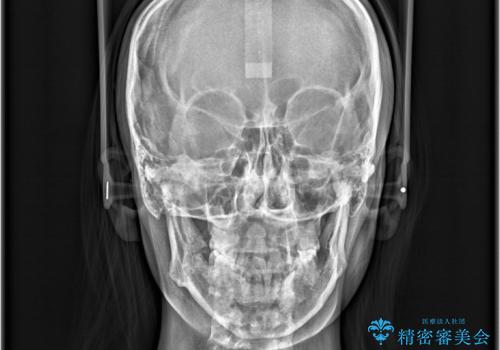

- 「歯の捻じれとがたつき」を主訴に来院された患者様です。

軽度な捻転と叢生だったため、インビザラインのモデレートで治療を行いわずか半年で治療を終える事が出来ました!